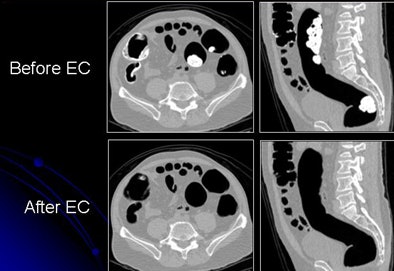

| Inhomogeneous tagging often appears in reduced or nonlaxative CTC. The uneven appearance of tagged materials on CTC data represents a mixture of semisolid fecal materials, air bubbles, fat, undigested foodstuffs, and unevenly distributed contrast agents. |

Inhomogeneous tagging often appears in reduced or nonlaxative CTC data, resulting from a mixture of semisolid fecal materials, air bubbles, fat, undigested foodstuffs, and unevenly distributed contrast agents.